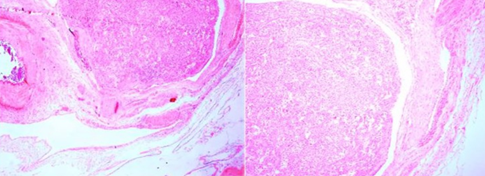

Histological image. Presence of stratified squamous epithelium without finding of skin adnexal structures (Courtesy Dr. V. Penopoulos)